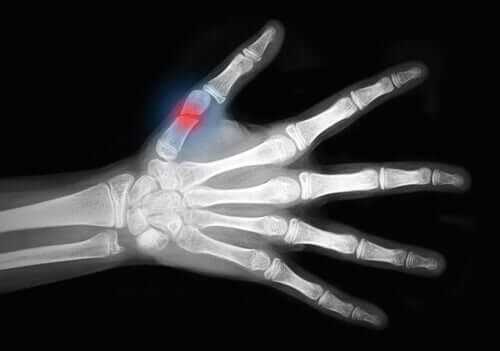

As lesões por desenluvamento são conhecidas na medicina como lesões traumáticas que rasgam os tecidos moles da pele em áreas extensas e expõem o osso. Elas afetam principalmente as extremidades.

Finalmente, temos as lesões de grau III. Elas estão associadas a danos graves na pele e nos músculos, como:

- Lesões vasculares;

- Síndromes compartimentais avançadas: é uma condição séria que envolve um aumento da pressão em um compartimento muscular. Pode levar a danos nos nervos e músculos, bem como causar problemas no fluxo sanguíneo.

- Lesões por esmagamento.

- Lesões por desenluvamento

Como podemos ver, as lesões por desenluvamento estão no grupo mais sério de classificação de lesões dos tecidos moles.

Lesões por desenluvamento precisam de grandes intervenções cirúrgicas. Algumas opções de tratamento incluem:

- Reimplante: juntar partes do corpo que foram amputadas. Por exemplo, os dedos.